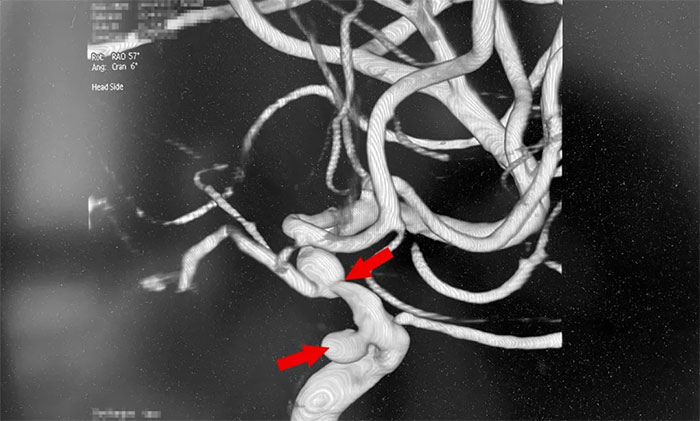

為進(jìn)一步明確診斷,王大媽接受了全腦血管造影DSA檢查,發(fā)現(xiàn)左頸內(nèi)動脈眼動脈段動脈瘤(約3mm)伴左頸內(nèi)動脈眼動脈段重度狹窄。神經(jīng)內(nèi)科4A病區(qū)主任席剛明教授、神經(jīng)內(nèi)科4A病區(qū)副主任王貴平博士會診指出,左頸內(nèi)動脈眼動脈段重度狹窄就是王大媽右側(cè)肢體活動不利等癥狀的“元兇”,如不及時解除血管狹窄,一旦頸內(nèi)動脈閉塞,就會發(fā)生腦梗死!此外,一旦腦動脈瘤破裂,將導(dǎo)致蛛網(wǎng)膜下腔出血!“左頸內(nèi)動脈眼動脈段重度狹窄”和“左頸內(nèi)動脈眼動脈段動脈瘤”就像潛伏在患者體內(nèi)的“不定時炸彈”,隨時都有被“引爆”的風(fēng)險,導(dǎo)致嚴(yán)重致殘甚至危及生命。

▲ 腦動脈狹窄合并腦動脈瘤